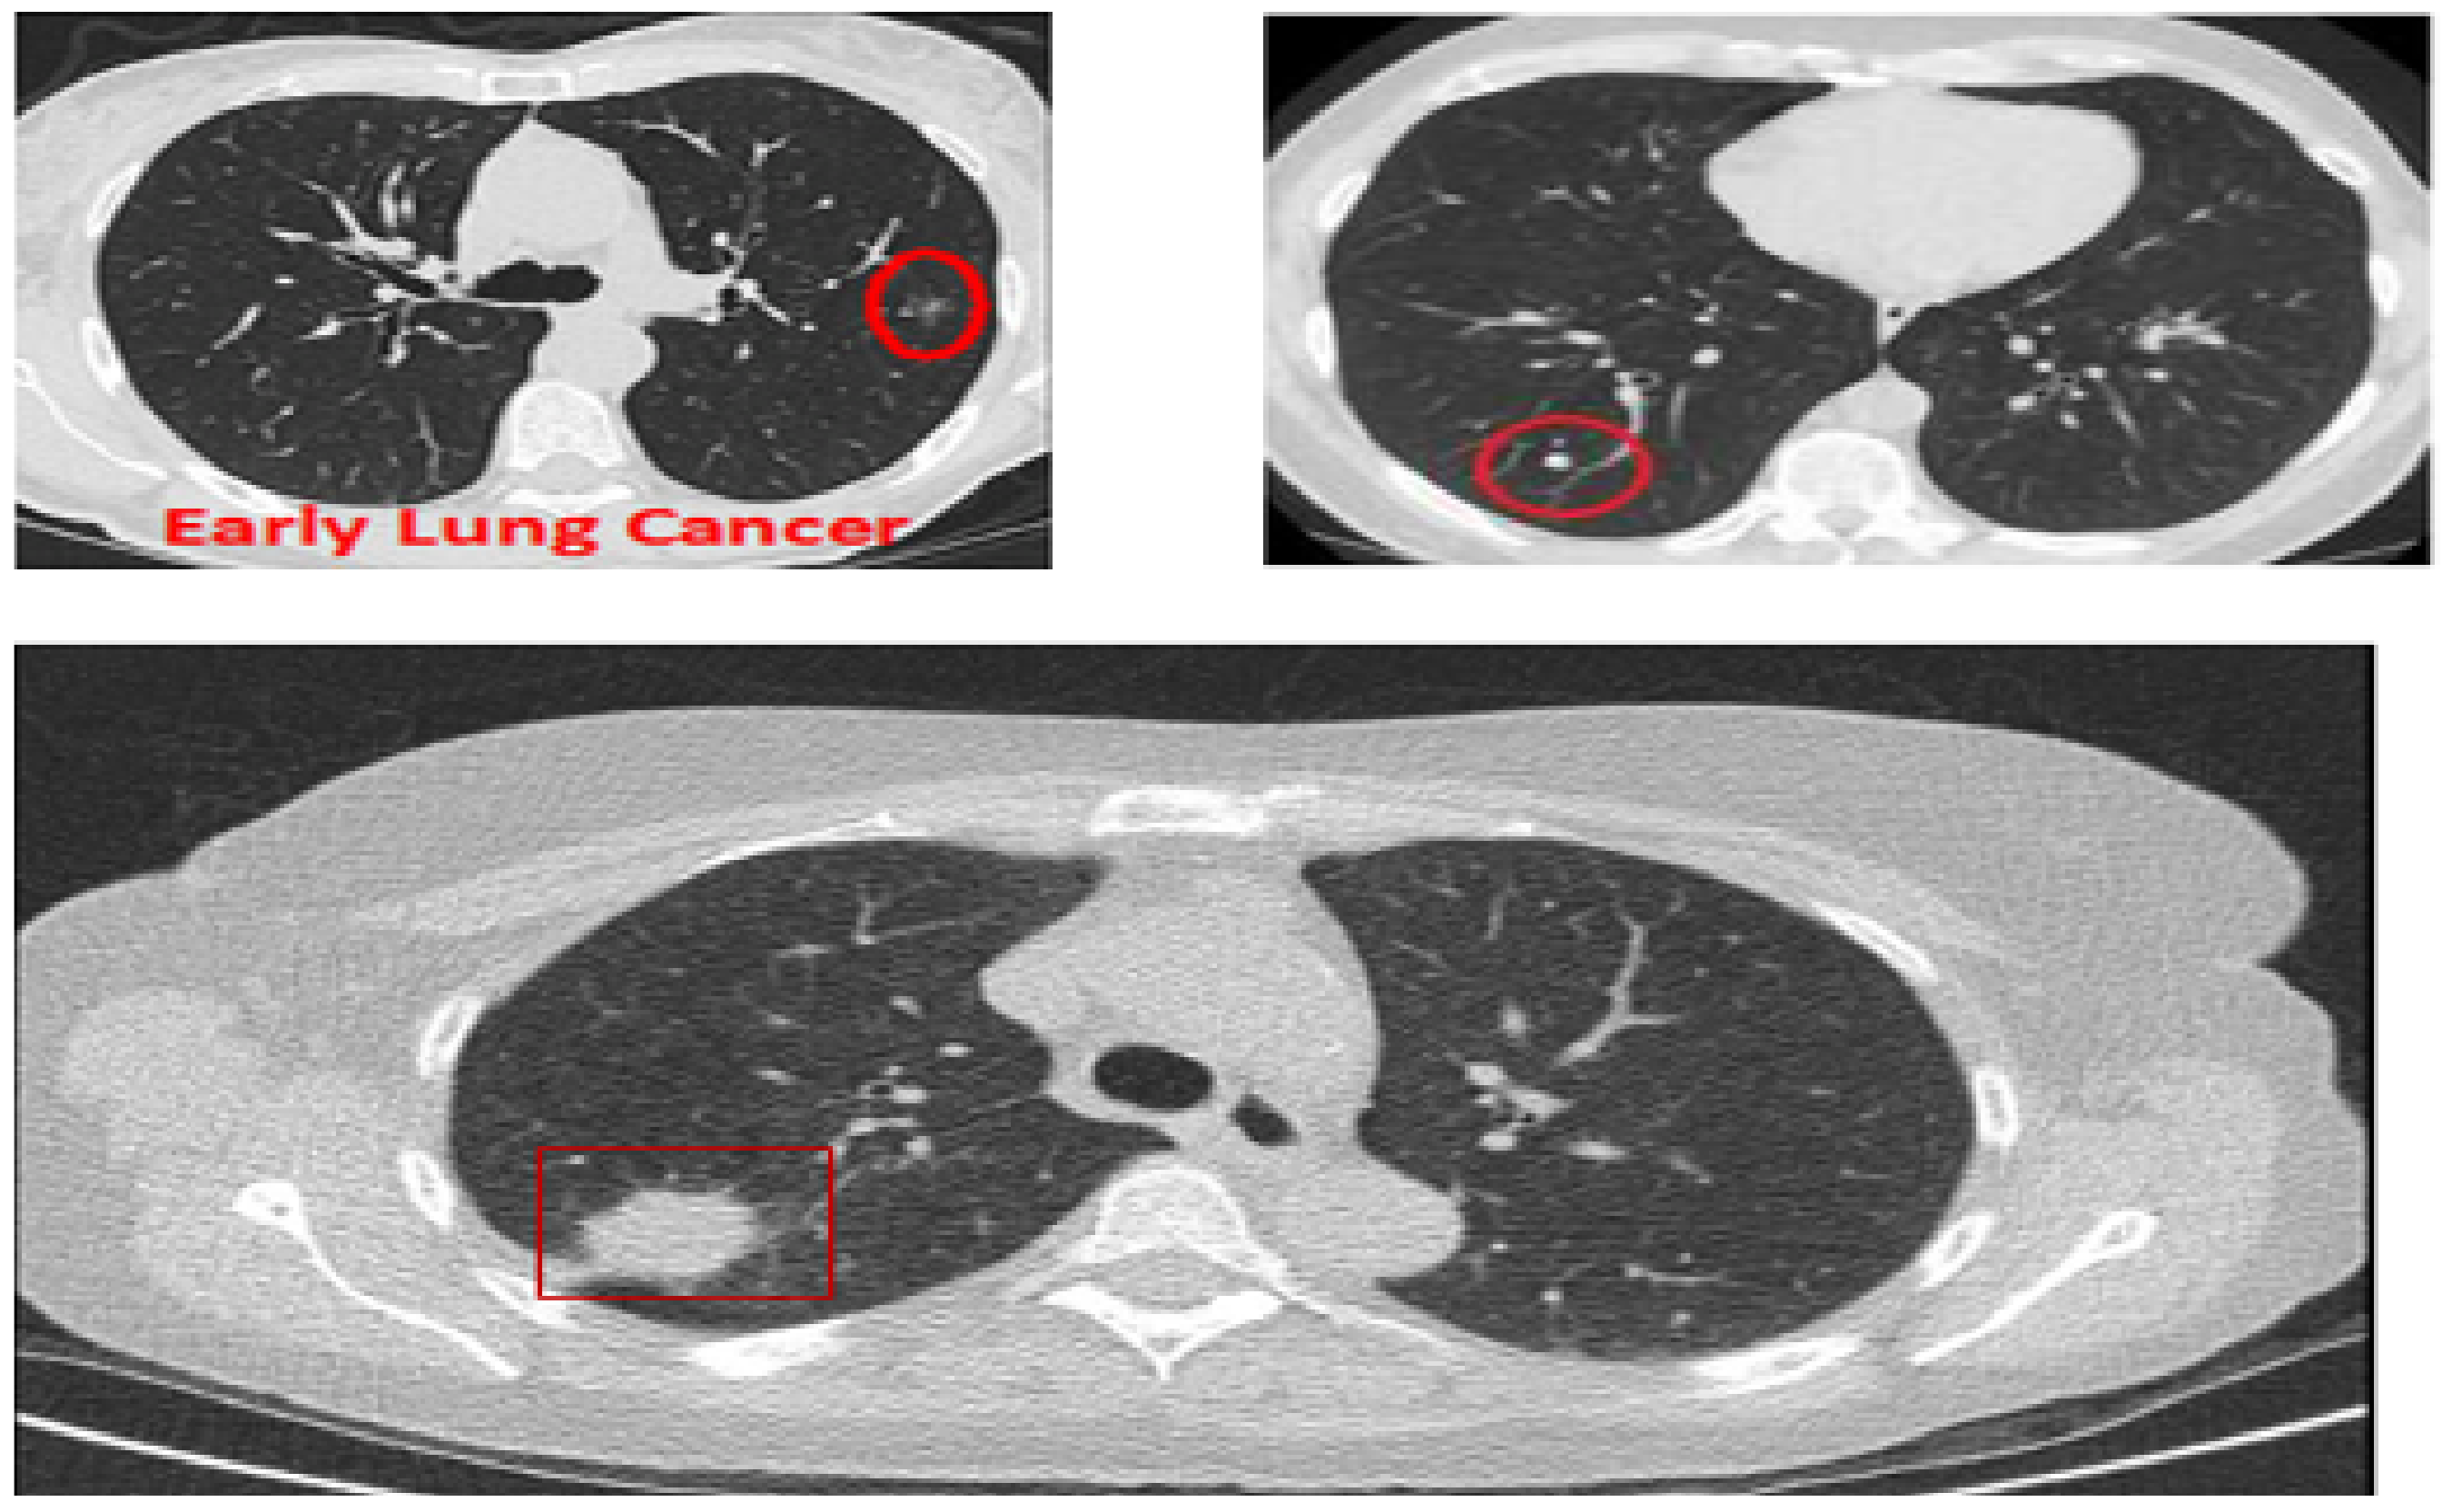

Although CAD systems demonstrate significantly high efficiency in lung nodule detection, the number of studies considering the routine workflow of radiologists is relatively low. Clinically, radiologists analyze the maximum projection intensity (MIP) images to locate the nodular candidates for further examination. MIP allows projecting 3-D voxels with maximum intensity to the plane of projection, thus enhancing nodule visualization [9]. MIP images are not threshold dependent and allow for preserving attenuation information [10], which helps convolutional neural networks (CNN) automatically detect lung nodules. In Figure 1, three CT images are shown: The top two show lungs containing early-stage cancer; the first being malignant and the second being benign. It is difficult to differentiate between vessel and cancer nodules during this stage. The last image is of cancer in its late stage, with a large nodule size making it easier to detect, but survival rates are low.

Figure 1.

CT scans based on maximum intensity projection.